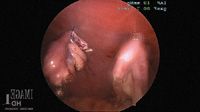

Photo 2: An intraoperative photo of a transected ovary (left) held to the body wall with percutaneously placed suture.

Once this procedure has been performed on both ovaries, remove the ovaries through an enlarged instrument port incision. Finally, inspect the abdomen for evidence of hemorrhage, and close the port sites routinely.